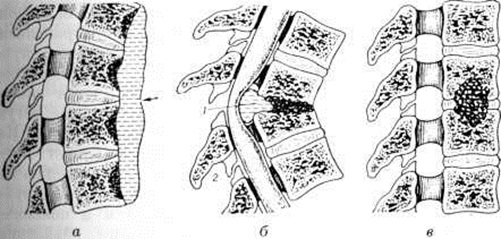

Возможны различные пути распространения туберкулёзного процесса из первичного очага через переднюю, заднюю и боковую поверхности тела позвонка (внедисковый путь), а также через межпозвоночный диск (внутридисковый путь). Процесс, распространяющийся внедисковым путем, приводит к обширным разрушениям позвонков. Прорываясь через переднюю поверхность тела позвонка, гной отслаивает переднюю продольную связку, распространяется под ней, образуя превертебральный абсцесс (рисунок 1, а), и вызывает контактное поражение других позвонков, так называемый поверхностную костоеду. Превертебральные абсцессы в зависимости от направления распространения гноя вызывают восходящий или нисходящий периостит (смотри полный свод знаний). При прорыве очага под заднюю продольную связку обычно возникают неврологический нарушения, обусловленные отёком спинного мозга (смотри полный свод знаний), сдавлением его гноем (рисунок 1, б), секвестрами, выступающими кзади остатками разрушенных позвонков, так называемый клином Урбана, утолщением мозговых оболочек вследствие пахименингита (смотри полный свод знаний). Характер неврологический нарушений определяется локализацией процесса и механизмом сдавления спинного мозга. При прорыве гноя через боковые поверхности тела позвонка образуются паравертебральные абсцессы, которые распространяются преимущественно в стороны от позвоночника и потому в меньшей степени контактно поражают тела соседних позвонков. В грудном отделе позвоночника такие абсцессы могут принимать форму веретена, полушарий, чечевицы, шаров, или так называемый ласточкиных гнезд (рисунок 2). В нижележащих отделах — нижнем грудном, поясничном и пояснично-крестцовом — абсцессы распространяются по мышцам, прикрепляющимся к пораженным позвонкам. Так, из поясничного отдела гной может распространяться в подвздошную область и далее — через мышечную лакуну на бедро. Из пояснично-крестцового отдела наиболее типичный путь распространения по ходу грушевидных мышц в ягодичную область. При внутридисковом пути процесс распространяется вертикально в направлении межпозвоночного диска, затем вовлекается студенистое ядро, а через него контактно — соседний позвонок (рисунок 1, в). Внутридисковое распространение гноя в большинстве случаев сочетается с малой деструкцией позвонков и наклонностью к отграничению процесса.